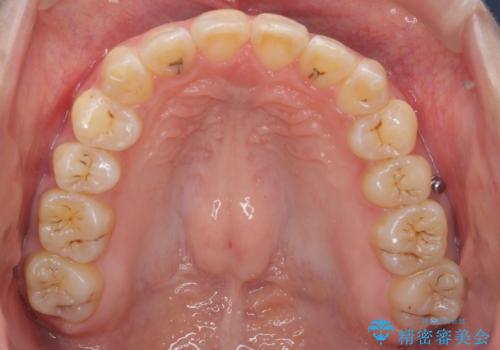

- 前歯の突出を主訴に来院。

上の奥歯を後ろに下げて治療をしました。

矯正用のミニスクリューを使用しています。

上の前歯もIPR(エナメル質をわずかに削る処置)を行っています。